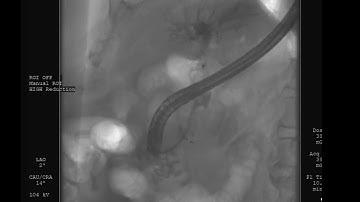

Cholangioscopy and Lithotripsy of Common bile duct stone